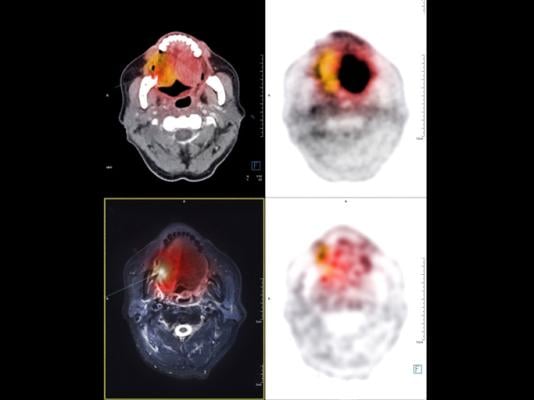

PET CT image of the Neck showing CA nasopharynx or carcinoma of nasopharynx from PET CT scannner. Getty Images